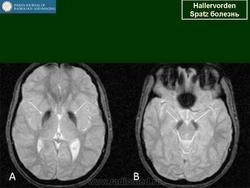

"Глаз тигра"-наглядно и красиво.

Вы правы. Выставил еще более нагладные исллюстрации.